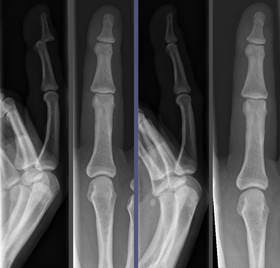

Joint dislocation in the DIP of the third finger before (left images) and after (right images) reduction. | |

Reduction is a surgical procedure to restore a fracture or dislocation to the correct alignment. This sense of the term "reduction" does not imply any sort of removal or quantitative decrease but rather implies a restoration: re ("back [to normal]") + ducere ("lead"/"bring"), i.e., "bringing back to normal." When a bone fractures, the fragments lose their alignment in the form of displacement or angulation. For the fractured bone to heal without any deformity the bony fragments must be re-aligned to their normal anatomical position. Orthopedic surgery attempts to recreate the normal anatomy of the fractured bone by reduction of the displacement.

Because the process of reduction can briefly be intensely painful, it is commonly done under a short-acting anaesthetic, sedative, or nerve block. Once the fragments are reduced, the reduction is maintained by application of casts, traction or held by plates, screws, or other implants which may in turn be external or internal. It is very important to verify the accuracy of reduction by clinical tests and X-ray, especially in the case with joint dislocations.